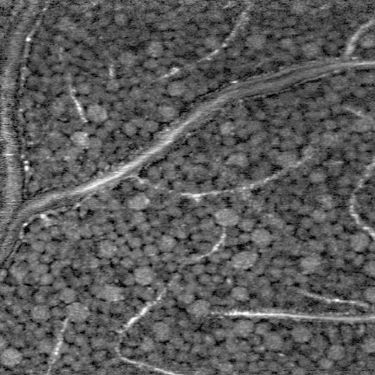

Zhuolin Liu, the first author on the paper describing the work and a research associate in Donald T. Miller's laboratory at the time of the study, says the new method is an optical microscope with extremely high resolution and sensitivity. It enables eye care practitioners to directly count retinal ganglion cells (the cells that die in glaucoma), allowing them to assess glaucoma damage long before current clinical instruments allow them to, she says.

"The cells are very small, highly translucent, and only dimly reflective. This prevents clinical instruments from creating sufficiently sharp images to see the damage," Miller says. "If eye care practitioners could see this damage earlier, when it affects individual cells, it could dramatically improve the diagnosis and treatment of glaucoma and other diseases of the retina."

The research team's method improves the performance of optical coherence tomography (OCT), which is the primary method used to detect eye disease in a clinic. Miller's laboratory obtains images that have higher resolution and higher contrast by using adaptive optics. The technology was originally developed in astronomy to remove the effects of atmospheric blur from telescope images.

"Our method provides a form of retinal biopsy," Liu says. "But it uses light, so it is noninvasive and allows repeated assessment of the same cells. By refocusing the instrument, we can obtain sharp images of cells at any depth in the retina, from cells on the surface to those that line the retinal bottom and keep the retina functioning."